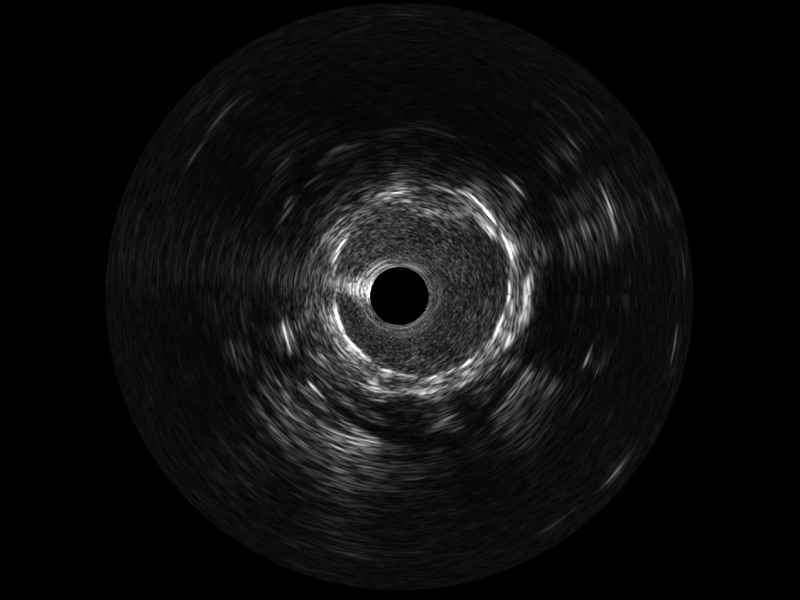

db真人体育官网宽频IVUS图像

传统IVUS图像

对比传统IVUS导管成像,db真人体育官网宽频IVUS图像的近场支架梁显影更细腻,远场中膜外血管仍清晰可辨,兼顾远中近,兼顾分辨力与穿透深度